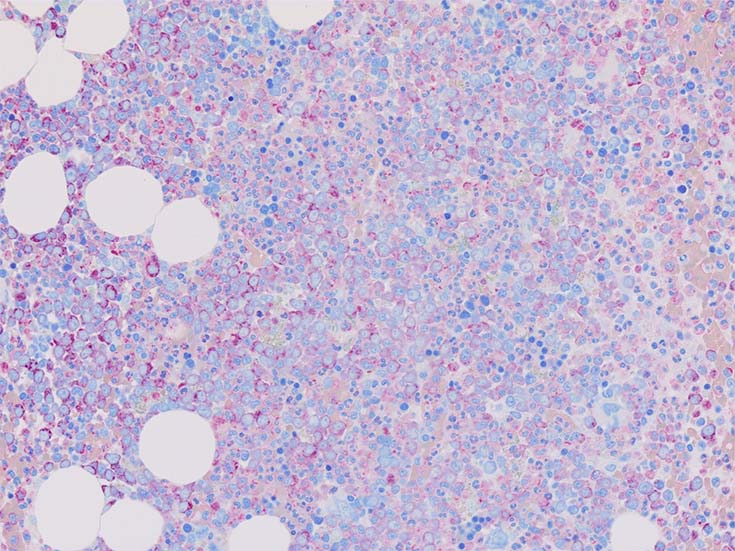

初診時の骨髄組織所見

thumb nail画像のクリックで大きな画像がみられます.

HE染色および, Naphtol-ASD-CAE染色した骨髄クロット組織標本-->Naphtol-ASD-CAE染色, 載せガラス法のページをみる.

70-80%のhypercellular marrow. 3系統造血細胞が認められる. Naphtol-ASD-CAE染色で赤色にそまる顆粒球系細胞増生が顕著な骨髄組織.

promyelocytesなど幼若顆粒球系細胞の集簇がみられるが, 分葉好中球他, 成熟顆粒球(Naphtol-ASD-CAE染色は薄く染まる傾向あり)も多く認められacute leukaemiaの所見ではない.

単球(Naphtol-ASD-CAE染色陰性)が密に増殖する所見は骨髄組織には認められない(*1)